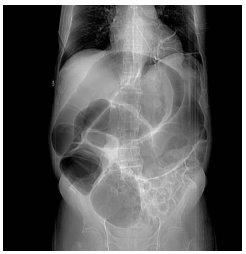

Mulher de 40 anos encontra-se no 4º dia de pós-operatório de hepatectomia parcial por nódulo hepático (em investigação diagnóstica). Apresenta dor abdominal em cólica, distensão abdominal gasosa e redução dos ruídos hidroaéreos. Refere dor em cólica que não tem aliviado com dipirona. Foi realizada a radiografia abdominal abaixo:

Qual o tratamento mais indicado neste caso?